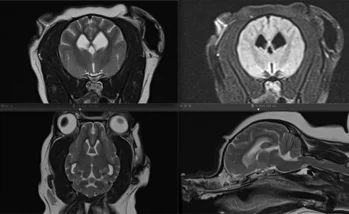

Neurologia

Gastroenterologia

Visite specialistiche:

Le visite specialistiche sono necessarie quando serve un approfondimento diagnostico in qualsiasi caso clinico complesso. In queste caso è fissato un appuntamento con un medico veterinario che si ocupa soltanto di quella branca.